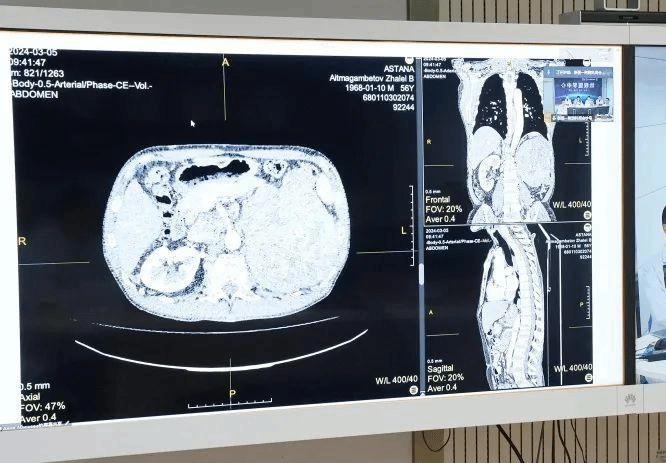

基于新疆医科大学远程医学平台,由新疆医科大学第一附属医院陆晨院长牵头,肾脏疾病中心、泌尿中心、肝胆包虫病外科、血管甲状腺外科、介入治疗中心、肿瘤中心、影像中心7个学科组成的多学科专家团队与哈萨克斯坦国立医学科学中心远程连线,就一例左肾巨大肿瘤合并重度癌栓的患者的治疗方案,展开深入讨论和分析。由于该患者癌栓已从左肾动脉波及股静脉、下腔静脉至右心房,病情复杂且经济条件有限,双方专家从各专业角度进行了全面分析,制定出适宜该患者的有效治疗方案,展现了在医疗领域更加高水平、深层次的紧密合作。